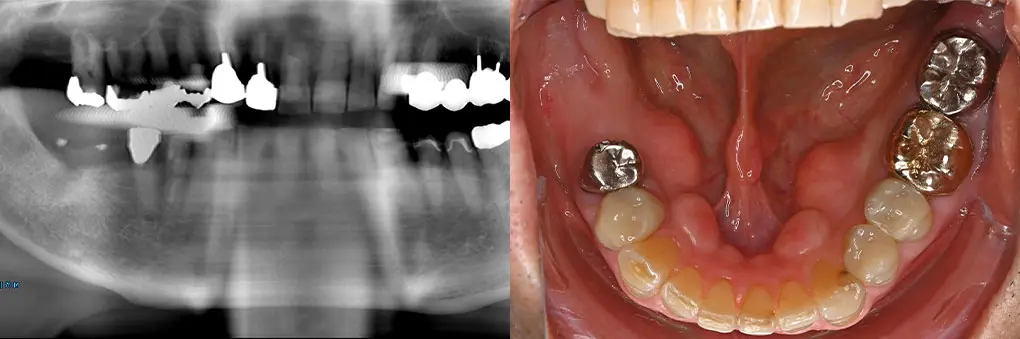

【症例4】入れ歯をインプラントで固定式ブリッジに(40代女性)

| 主訴・背景 | 取り外し式の入れ歯をインプラントで治療したい |

|---|---|

| 診断・治療前の状態 | 抜歯後2カ月のため抜歯窩が存在 矯正治療後前歯部歯根が吸収して、歯の動揺がひどくなり可徹式義歯を装着 |

| 治療方針・計画 | インプラント埋入と同時に骨造成術を併用 |

| 手術・処置内容 | ⚫︎ 治療部位13,11,22 インプラント3本 ⚫︎ 骨造成術を併用治療 ⚫︎ ストローマン社 BL BLT ⚫︎ 上部構造 ジルコニアセラミックブリッジ |

| 治療期間・回数 | 仮歯装着まで2カ月、最終補綴装着まで2カ月、トータル4カ月/6回 |

| 費用・料金(自費診療の場合) | 1,800,000円 |

| リスク・注意点・術後ケア | セラミックの破折、インプラント周囲炎、定期検診 |

| 治療後の状態・経過写真 | 「違和感なく以前の自身の歯よりきれいになりました」 現在、7年経過良好。遠方からの来院のため6カ月定期検診 |

| まとめ・院からのコメント | 学生時代に矯正治療を受け20年後歯の動揺が出現し、近医で抜歯、可徹式義歯装着と失望感が強かった患者様が笑顔になり嬉しく思います。 |